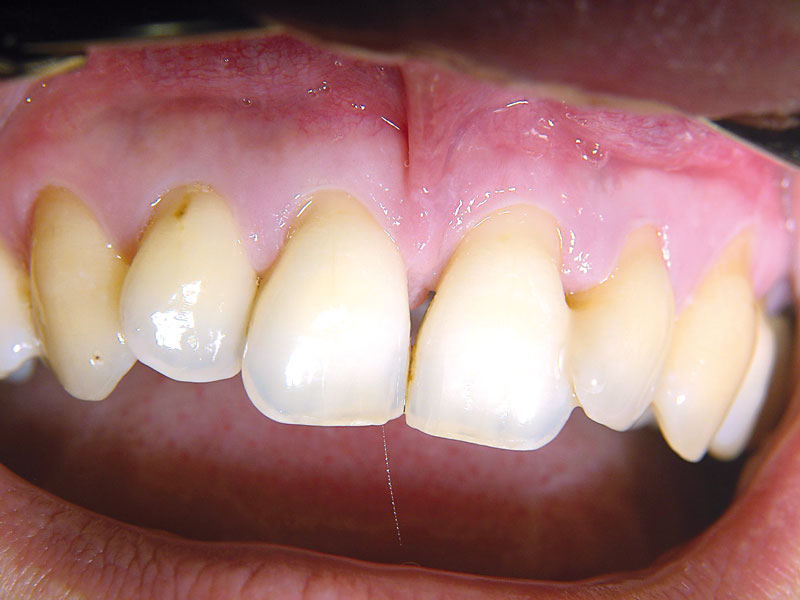

02/11 - Baseline clinical situation.Non-contained intrabony defect treated using cerabone®, collprotect® membrane and Straumann® Emdogain® - Dr. T. Schwaar (2)